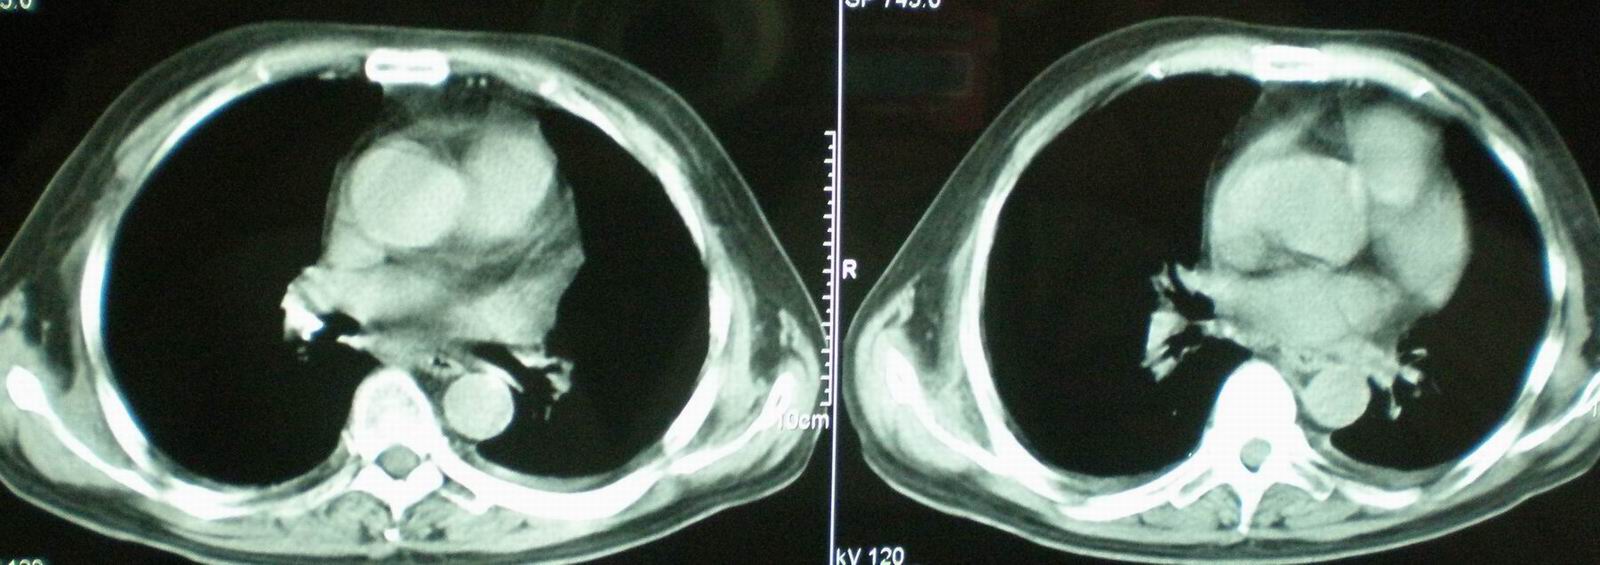

2008年11月18日今天的ct片

2008年9月18日ct片

2008年9月8日ct片:

[face=宋体]显然上级医院进行了抗结核,抗真菌,抗炎等治疗,目前病人肺内病灶基本消失,双侧胸腔积液,右侧积液量有吸收,抗结核一个多月,现在病人疑问,结核的诊断是否有疑义,抗结核是否继续,因为那个毕竟副作用大。[/face]

我仔细看了下病人的出院小结,当时情况危急,诊断里有1型呼衰。心包周围的是脂肪密度。结合三次ct扫描的图象分析,个人认为:1、病人目前肺部病灶基本消失,双侧胸腔内少量积液,抗结核治疗才一个多月,就算是结核,抗结核治疗有效果,为何效果如此好,一点纤维灶的痕迹都没有呢,再就是患者做过气管镜检查及活检、痰检均未找到结核的证据。所以不支持结核的诊断。

2、结合现在的ct片,考虑:肺水肿及真菌感染,双侧胸腔积液。

机遇性感染。双肺实质满布。且以肺门周围为主。不象结核。